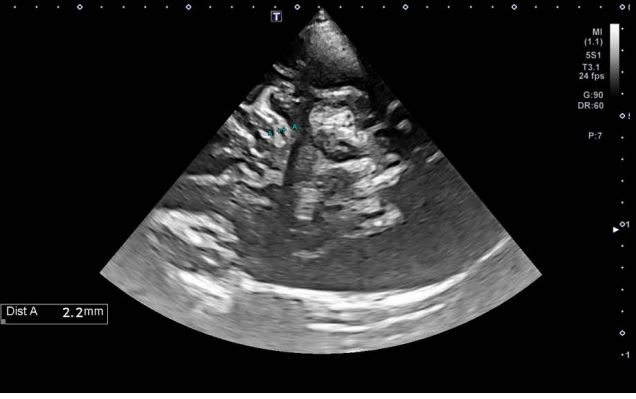

Вивчення проблеми 1

Хворий з наявністю набряку зорового нерва (1,3 мм), ОНС>6,8 мм. Клінічну картину внутрішньочерепноїгіпертензії доповнює вивчення зміщення середньої лінії, яке виділяє явну дезорієнтацію головного мозку: 73,5 – 57,3 = 16,2/2= 8,1 (Мал. 1).

Малюнок 1 Висновок застосування ультразвукового дослідження в клініці: обстеження цього пацієнта було консервативним, тому ультразвукове дослідження дозволяє контролювати морфологічні зміни.